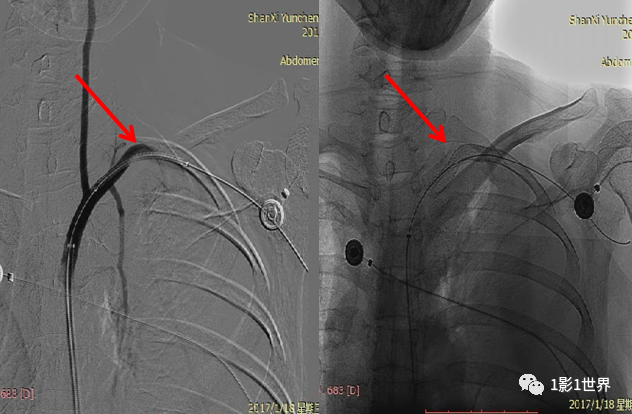

中年男性,因经常性头晕伴左上肢无力、肢体发凉就诊。查体:双上肢脉压差较大,收缩压左侧较右侧低40mmHg,左侧桡动脉搏动较弱、皮温略低。临床怀疑锁骨下盗血综合征,首先行CTA检查,发现病变,后经DSA血管造影证实,最后诊断:左侧锁骨下动脉近端狭窄(>75%)。

本例,介入科行“左侧锁骨下动脉支架植入术”,术中先行狭窄处球囊扩张,造影显示扩张满意后置入支架。术后,患者立即感到左上肢温暖,第3天出院。